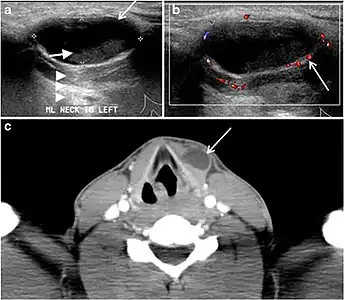

Fig. 4. A 45-year-old male patient presented with anterior mediastinal metastatic PTC lesions and occult primary on imaging. Histopathology examination of the resected thyroid gland revealed micro-foci of PTC; the largest, in the isthmus, measured 4 mm. a transverse greyscale ultrasound of the thyroid demonstrates homogeneous gland with normal echogenicity and size. No focal lesion or micro-calcifications. b Non-enhanced CT scan obtained as part of PET/CT examination shows a heterogeneous, large, relatively dense anterior mediastinal mass (white arrow) with peripheral calcification (arrowheads). Thyroid gland has normal CT appearance with no abnormal FDG uptake (not shown).[1]